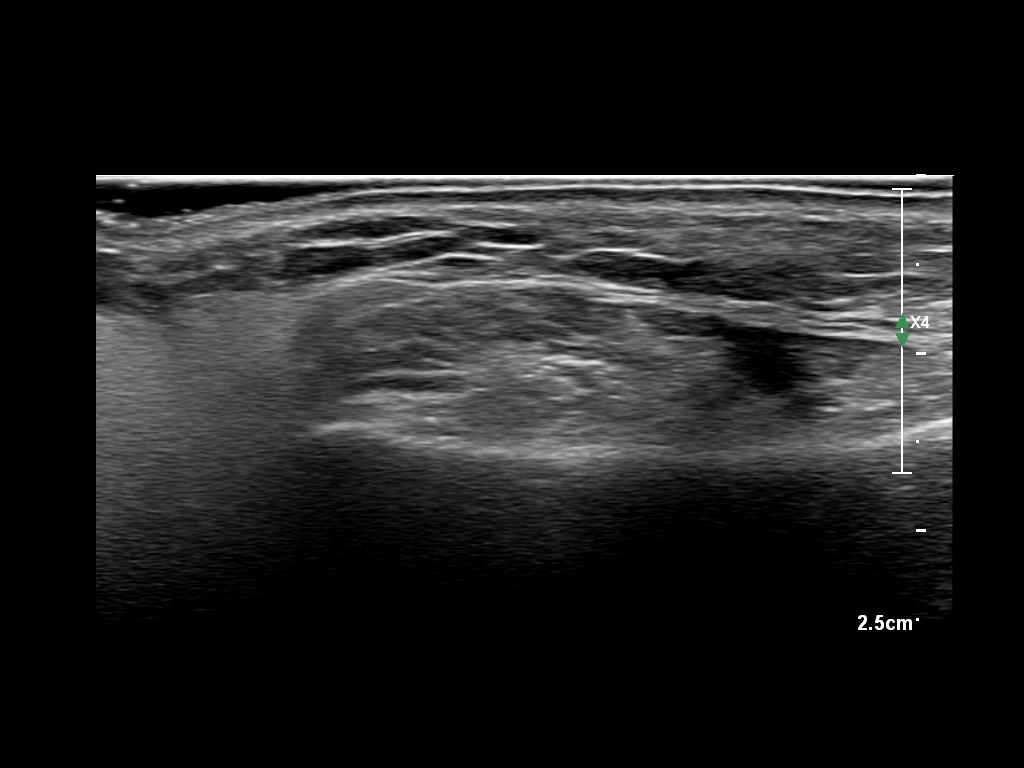

Fillers

Draw in the image on the right where the fillers are located. To check if your answer is correct, please click on the secondary image.

Fillers

Draw in the second image below where the fillers are located. To check if your answer is correct, swipe the first image to the right.

HAca 1a

HAca 1b e